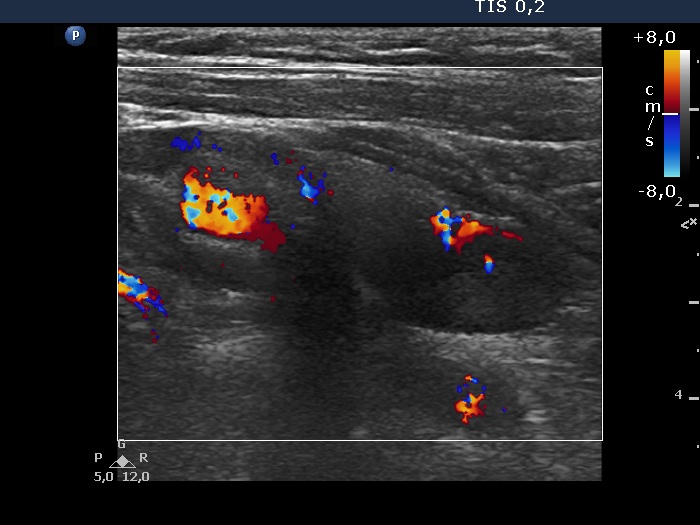

Right lobe, longitudinal scan

Left lobe, longitudinal scan, color Doppler mode. There is a large vessel running in the ventral part of the lesion.